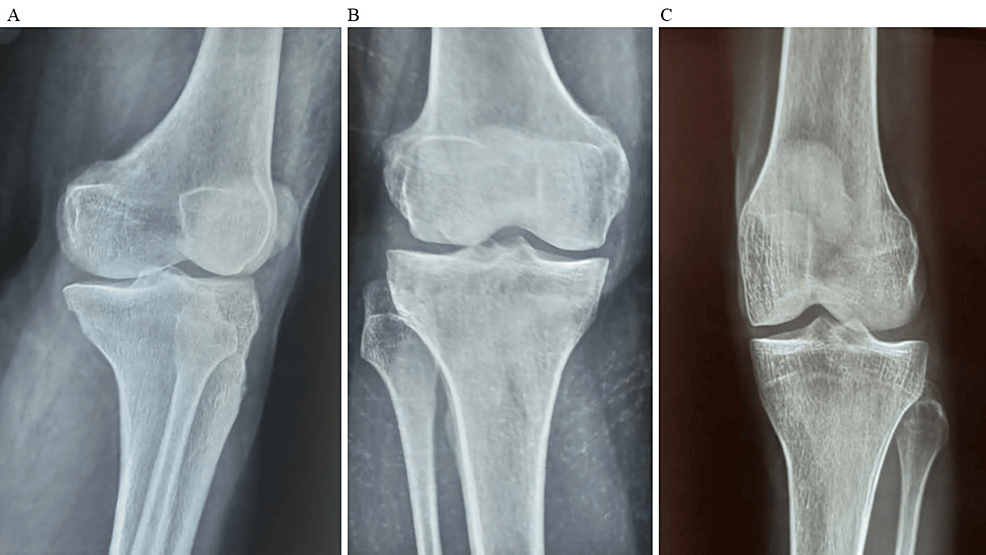

平均WOMAC評(píng)分從基線時(shí)的56.8±11.5下降到六個(gè)月時(shí)的41.2±10.6。此外,還監(jiān)測(cè)了不良事件的發(fā)生情況,報(bào)告了七起不良事件,占參與者的28.0%。這些發(fā)現(xiàn)強(qiáng)調(diào)了該治療在六個(gè)月內(nèi)減輕疼痛和改善功能結(jié)果方面的有效性。下圖2顯示了開始干細(xì)胞治療后骨骼的側(cè)視圖和前后視圖。?

圖2:顯示了開始干細(xì)胞治療后骨骼的側(cè)視圖和前后視圖

圖2:A:干細(xì)胞治療后(側(cè)視圖),B:干細(xì)胞治療后前后位 (AP) 視圖,C:干細(xì)胞治療后前后位 (AP) 視圖。